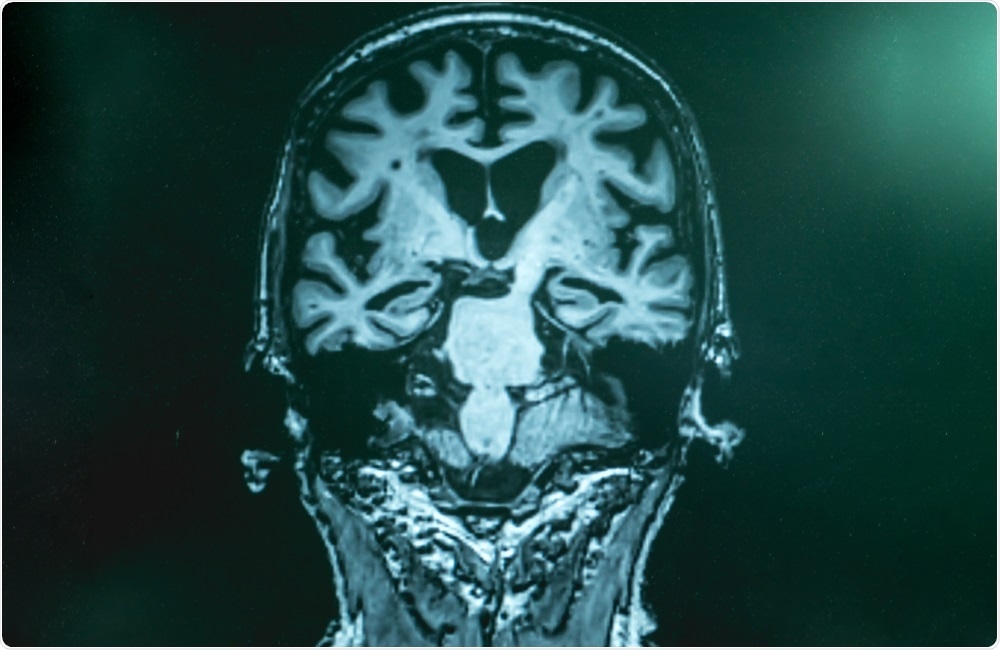

Atthapon RaksthapuImage Credit: Atthapon Raksthapu / Shutterstock

The data included clinical information, magnetic resonance imaging (MRI) testing and genetic assessments.